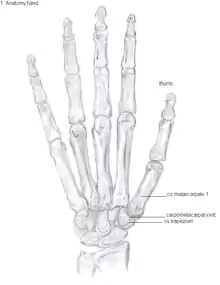

Showing the bones of the hand

Anatomy

The TMC joint is a synovial joint between the trapezium bone of the wrist and the metacarpal bone at the base of the thumb. This joint is a so-called saddle joint (articulatio sellaris), unlike the CMC joints of the other four fingers which are ellipsoid joints.[17] This means that the surfaces of the TMC joint are both concave and convex.

This shape provides the TMC joint a wide range of motion. Movements include:[18]

The TMC joint is stabilized by 16 ligaments.[19] Of these ligaments, the deep anterior oblique ligament, also known as the palmar beak ligament, is considered to be the most important stabilizing ligament.[20]